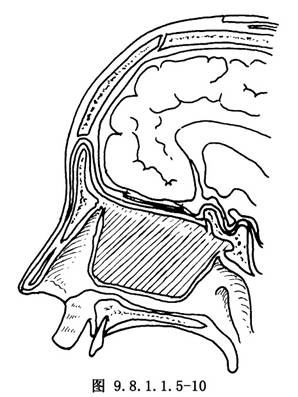

(1)顱腔術區關閉:清潔沖洗顱內術區,確實封閉硬腦膜裂口和缺損。製作額部腱膜瓣,蒂留於下方(圖9.8.1.1.5-8),由骨窗下緣轉入顱內,並於蝶骨平板和雙側眶板切緣處鑽孔縫合(圖9.8.1.1.5-9)。去除顱內敷料,大腦額葉復位,額骨瓣復位,鋼絲固定。復位額顳組織瓣,分層縫合(圖9.8.1.1.5-10)。前顱底缺損區,除硬腦膜修復外,又轉入了較厚的額部腱膜瓣,故骨缺損較小時可不作硬組織修復,但骨缺損區過大,則應用骨組織修復。